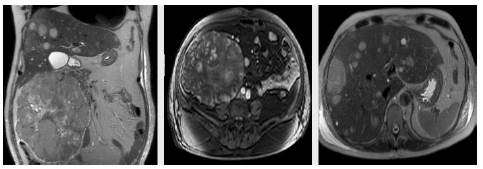

Initially, management was given to compensate for heart failure. Considering his medical history and the presence of a mass in the upper right lobe, a computed tomography (CT) of the thorax was performed in which a mass in the upper right lobe of 38x29x29mm was observed, without enhancement after the administration of contrast medium. It also showed three other nodular images with the same characteristics in the apical segment of the upper left lobe with a secondary neoplastic aspect (Figure 1).

CT scan of the chest.

Figure 1: CT scan of the chest.

Source: Document obtained during the study.